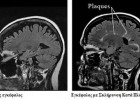

Σκλήρυνση κατά πλάκας: Ποια είναι τα πρώτα σημάδια

Τι ακριβώς είναι η σκλήρυνση κατά πλάκας και ποια είναι τα κυριότερα (αλλά και όχι τα πιο συχνά) συμπτώματά της; Η σκλήρυνση κατά πλάκας είναι μια ασθένεια με...